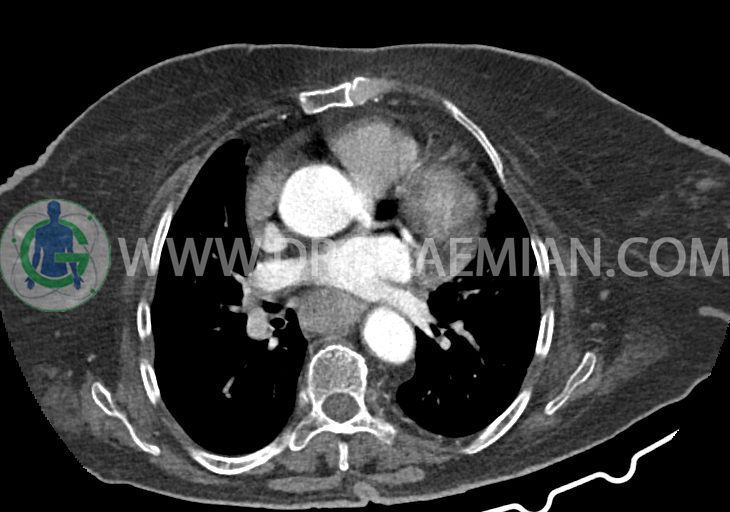

بیمار کنسر مری دارد و برای بررسی متاستاز مراجعه کرده است.

–دیلاتاسیون نیمه فوقانی مری توراسیک ناشی از افزایش ضخامت circumferential توده مانند در یک سوم دیستال مری به طول 50mm ، که می تواند مطرح کننده انفیلتراسیون تومورال همراه با تنگی

–تصویر یک ناحیه نسج نرمی با ابعاد تقریبی 37x22mm ، که بنظر از جدار قدامی قسمت دوم دئودنوم برخاسته است و واجد ناحیه هایپردنس متالیک با آرتیفکت Streak ( با HU= 20000 ) مطرح کننده دیورتیکول دئودنوم، حاوی جسم خارجی و یا باریوم باقیمانده و غلیظ شده از مطالعات قبل